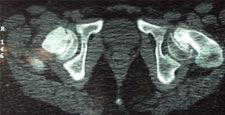

Slipped Capital Femroal Epiphysis (SCFE)

SCFE is a common hip pathology seen more frequently in boys than girls during the adolescent growth spurt. There is a mechanical weakening between the met- aphyses of the femoral neck and head causing the epiphysis to slip posteriorly.

It is more common in children with endocrine disorders, with metabolic bone disease and renal disorders. Children with bilateral slips must be evaluated for thyroid and, growth hormone deficiency and renal causes SCFE may vary from mild (early) slip to moderate and complete slip depending on the extent of displacement of epiphysis. SCFE can also be classified as Stable and Unstable slips depending on the ability of the child to bear weight on the affected leg.

Any acute, and unstable SCFE requires emergent treatment. Stable slips also need to pinned on an elective basis. Untreated or unreduced SCFE can lead to Avascular Necrosis of the epiphysis, chondrolysis and Femoral-Acetabular impingment leading to early hip arthritis. Severe Slip may required open reduction using the Anterior or Watson-Jones Approach or the Safe-Surgical Hip (GANZ) Dislocation approach.

SCFE treated with the Ganz Approach